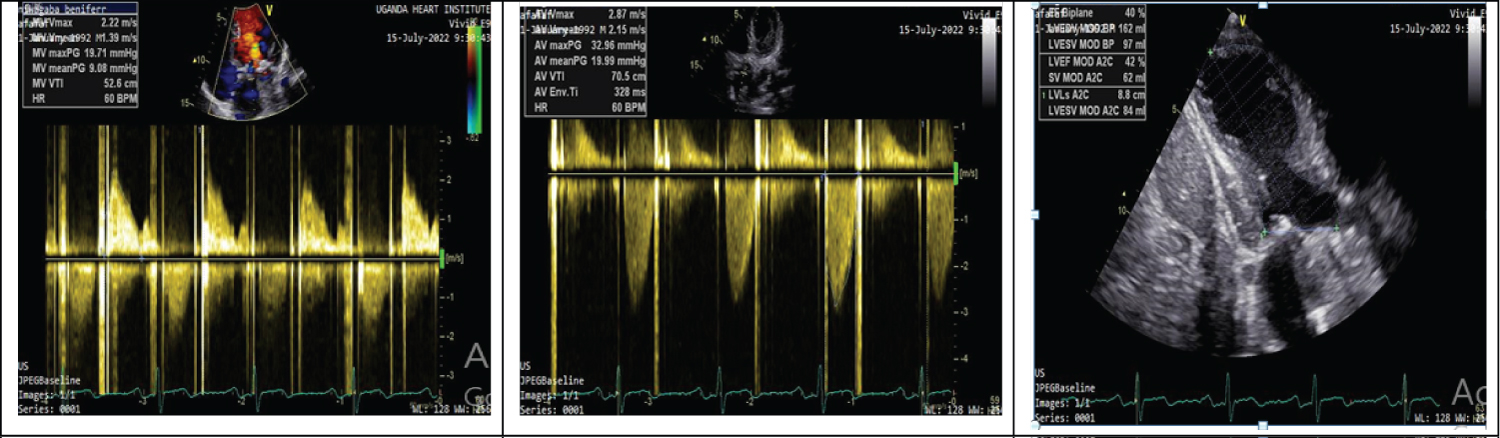

The trans-thoracic echocardiogram done prior to the coronary intervention revealed normal cardiac chambers, mild hypokinesia in the mid left ventricular antero-septal segments with mild Left ventricular systolic dysfunction. The mechanical prosthetic valves in the mitral and aortic valve positions were visualized with normal disc motion of the respective valves, with mildly elevated pressure gradients (PGs) across both valves for which mitral valve mean/max-9/19 mmHg and Aortic valve mean/max-19/32 mmHg (Figure 2).

Figure 2: a) Mitral valve PGs; b) Aortic valve PGs; c) Mod LV systolic dysfunction. View Figure 2